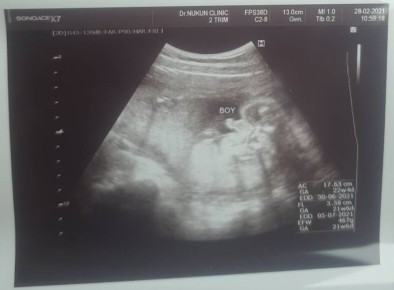

ผม ผู้ชาย ค้าบบ ^^

ผช.ค้าบบ 31+4week

ผู้ชาย15+6 คาป